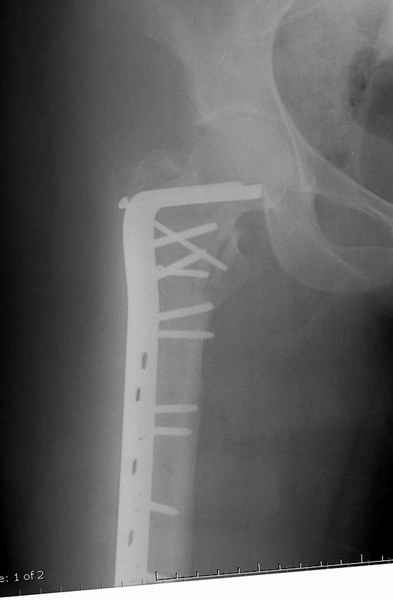

Большие преимущества у интрамедуллярных штифтов, метод хорош и можно произвести из минимального доступа, но во время операции необходимо контролирование варуса, затем приступить к блокированию.

слайды:

Long TFN

Short TFN

IMHS

DePuy Trochanteric Nail

Контролировать варус